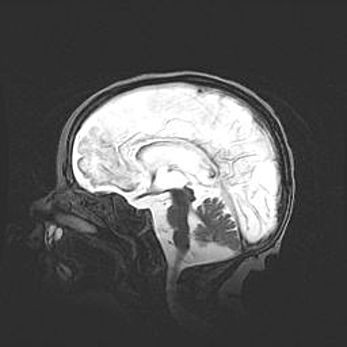

Аномалия Денди-Уокера. Признаки гипоплазии мозолистого тела.

Возраст: 5 месяцев 3 дня

Вес: 5550 г

Пол: мужской

Окружность головы: 39 см

Срок гестации: 40 недель

Аномалия Денди-Уокера – это порок развития головного мозга, для которого характерна триада симптомов: гипотрофия или аплазия червя мозжечка и/или полушарий мозжечка, расширение четвёртого желудочка с формированием ликворной кисты задней черепной ямки, гипертензионная гидроцефалия различной степени.

Гипоплазия мозолистого тела относится к дефектам внутриутробного этапа развития мозговой ткани, возникающим в процессе закладки структур головного мозга, что происходит на начальных этапах развития эмбриона.